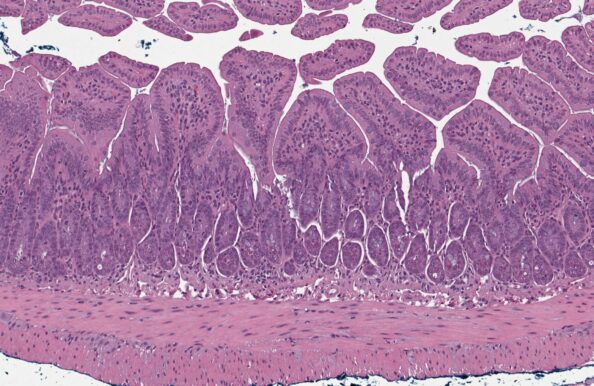

구브라는 염증성 장 질환 (IBD)과 장 섬유증 연구를 위한 비임상 모델로 업계를 선도하고 있습니다. 구브라의 만성 덱스트란 황산나트륨 (DSS) 모델을 이용해 IBD 대상 약물의 소염 및 항섬유증의 효능을 테스트하세요.

구브라는 염증성 장질환(IBD)의 예방 및 치료적 개입 연구를 위한 최첨단 DSS 마우스 모델을 제공합니다. 또한 고급 인공지능 기반 조직학적 기술을 사용하여 약물의 치료 효과를 분석해드립니다. 구브라의 새로운 만성 DSS-IBD 마우스 모델과 대장 섬유증 모델을 지금 확인해보세요.

급성 궤양성/염증성 대장염의 표준 모델

대장 특이적 점막 표피 손상의 급성 발현

입체학적 기반 조직병리학적 분석

섬유증을 동반한 만성 IBD의 최첨단 모델